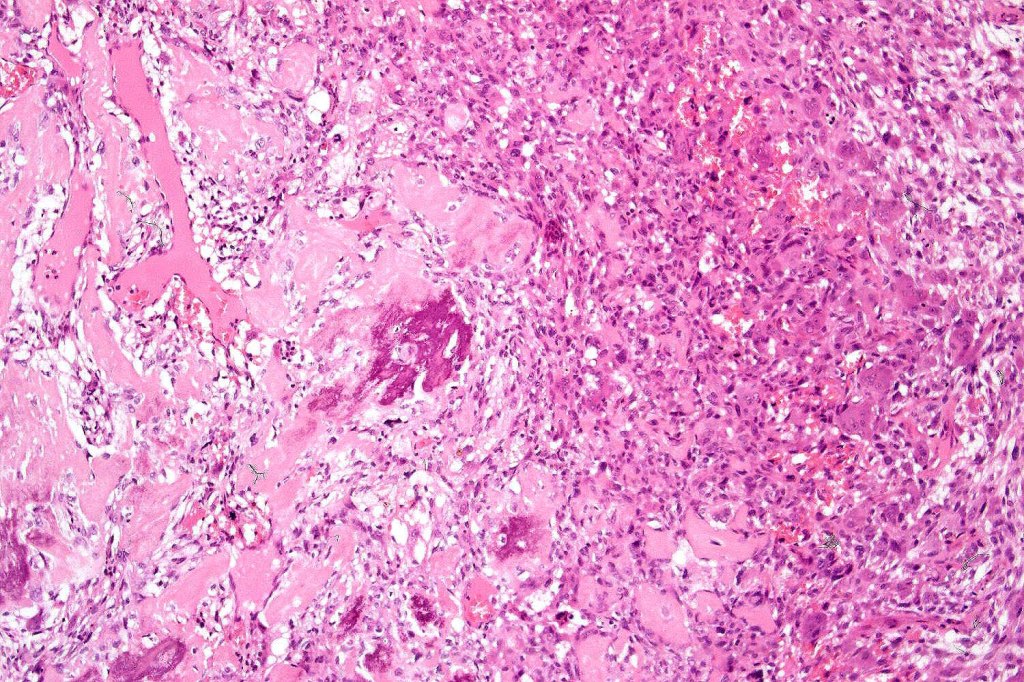

Carcinosarcoma

Cutaneous carcinosarcoma (metaplastic carcinoma, carcinoma with heterologous differentiation)

Histological features

•Osteoid

•Chondroid

•Smooth muscle

•MFH-like features with osteoclasts

•Neural differentiation